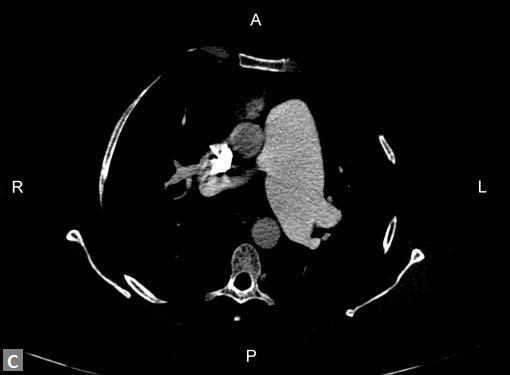

On occasions, thromboembolism can also be seen in right

ventricle and less commonly in pulmonary veins. Systemic

vein thrombus (innominate veins, SVC, IVC) sometimes

accompanies pulmonary thromboembolism (Figs 18A and B).